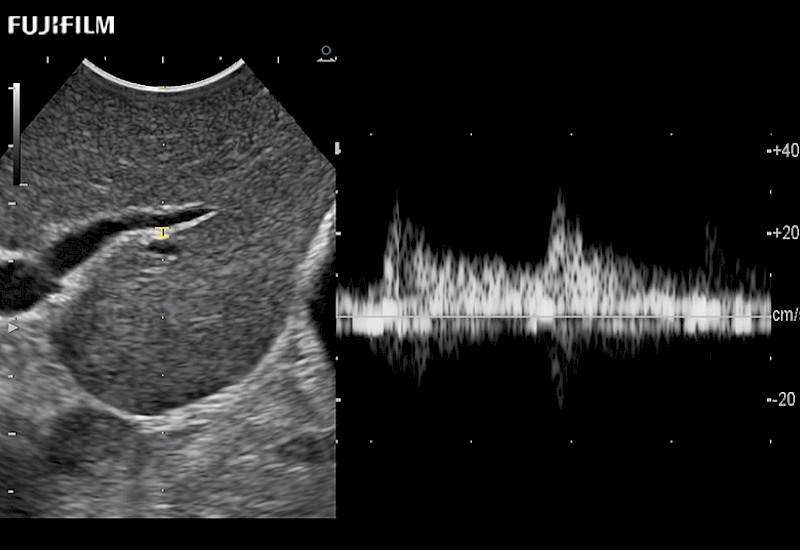

Multi-Parametric imaging modalities

The ARIETTA 750 incorporates all of the proven technologies and functions that medical professionals have come to expect from Fujifilm Healthcare.

ARIETTA 750 is the definitive diagnostic ultrasound solution for any clinical setting - Private Office, Imaging Center, or Hospital. The ARIETTA platform provides the ultimate in clinical performance with its state-of-the-art features and large user-friendly display.

The ARIETTA 650 DI combines trusted Fujifilm Healthcare technologies and features tailored for surgical oncology.

Designed to meet the demands of surgeons, the ARIETTA 650 DI offers precise guidance. Its advanced capabilities and large, intuitive display offer accurate and efficient care in operating rooms and specialized surgical settings.

Fujifilm Healthcare continues to listen to the experts, our neurosurgeons, by developing an ultrasound system specifically designed for the Operating Room.

Guidance is the fundamental purpose for all of our surgical ultrasound technology. Fujifilm Healthcare is committed to designing tools that help neurosurgeons navigate inside the human body and provide the necessary information to immediately make critical surgical decisions.

With the ARIETTA Precision the next level of surgical ultrasound is here.